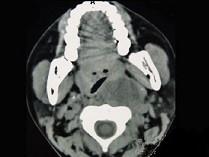

问题 女性,34岁,自诉1个月前被咽喉部被鱼刺刺伤,近半个月发热,咽喉部疼痛,CT检查如图所示,请选择正确的描述和结论 ( )

选项 A、考虑神经源性肿瘤 B、考虑血管瘤 C、肿块内密度均匀 D、考虑咽后壁脓肿 E、左侧咽后壁可见低密度肿块影

答案 CDE